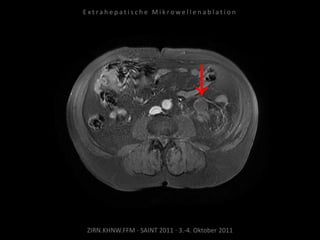

Kontrollbildgebung:

MRT 10.09.2010

Verlaufskontrolle:

CT 21.10.2010

MRT 21.01.2011

MRT 08.04.2011

Zunehmende Tumoraktivität der

Metastase kaudal der linken Niere

ohne signifikante Größenzunahme.